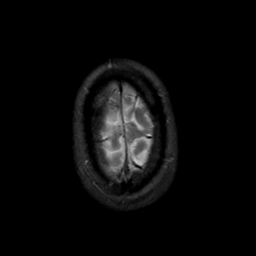

MR Study #19, August 25, 1991 -- Slice #46

[Home][Help][Clinical][Tour 1][Tour 2] Slice 46